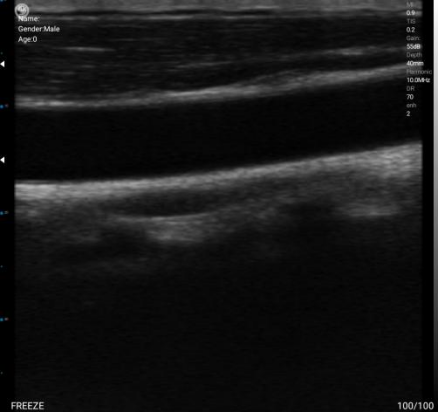

In sonograms, various echo imaging patterns are primarily caused by differences in acoustic impedance. As shown in the figure above, due to the high acoustic impedance of bones, they appear as high echoes on the image. The general order of acoustic impedance values is: Air <Fat <Water <Blood <Kidney <Liver <Muscle <Skin <Bone